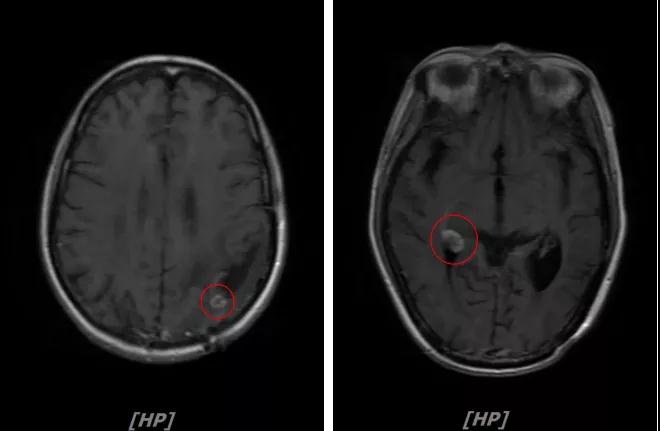

每3个月规律复查,未见明显异常。如2015年8月 头颅MR检查,提示:左顶叶脑转移瘤术后放疗后改变,对比前片2015年3月10日相仿。